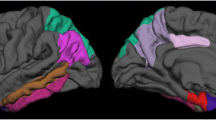

MRI atrophy predicts cognitive status in AD. However, this relationship has not been investigated in early-onset AD (EOAD, < 65 years) patients with a biomarker-based diagnosis.

In EOAD, hemispheric CTh and ventricular volume at baseline were associated with global cognition, language and attentional/executive functioning 2 years later (p < 0.0028). Regional CTh was related to most cognitive outcomes (p < 0.0028), except verbal/visual memory subtests. Amygdalar volume was associated with letter fluency test (p < 0.0028). Hippocampal volume did not show significant associations.

Baseline hemispheric/regional CTh, ventricular and amygdalar volume, but not the hippocampus, predict two-year cognitive outcomes in EOAD.